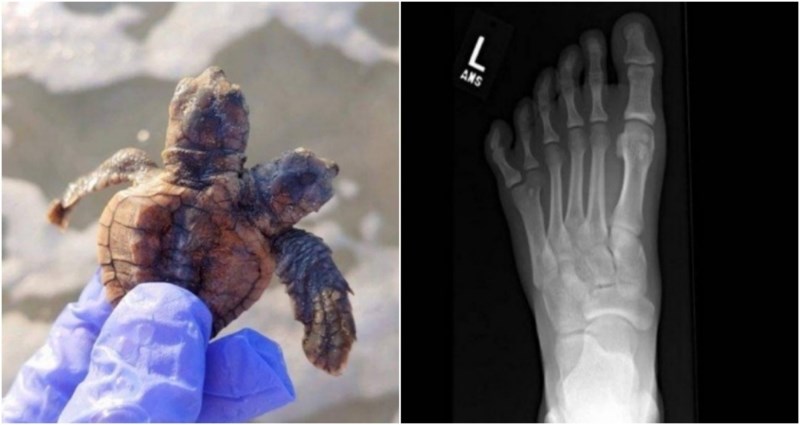

13. Rendgenska snimka stopala s 6 prstiju

14. Pronašli smo sijamske blizance morske kornjače! Pustili smo ih natrag u ocean. Sretno!